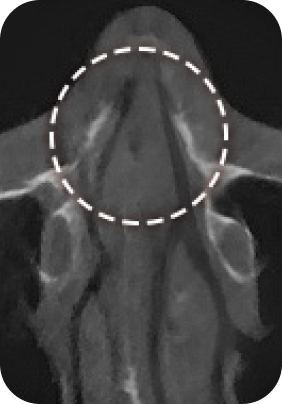

맘모톰, 비후성/알레르기 비염, 비중격 만곡증, 비밸브 협착증 등

질환에 따라 3DCT, 내시경 검사, 고해상도 초음파를 통해 정밀진단 후

정확한 증상에 따라 보험 실비 청구가 가능합니다.

대학병원급 검사 장비

디에이성형외과에서는 대학병원급 검사 장비 시스템

각 분과의 전문의와 성형외과 전문의가 협진하여